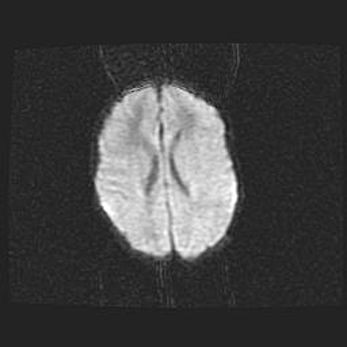

Сообщающаяся гидроцефалия. Кистозная энцефаломаляция головного мозга.

Возраст: 3 месяца 4 дня

Вес: 3100 г

Пол: женский

Окружность головы: 34 см

Срок гестации: 31 неделя

Кистозная энцефаломаляция головного мозга - одна из форм поражения головного мозга в детском возрасте. Характеризуется возникновением множественных и распространённых кист в коре, белом веществе и подкорковых образованиях головного мозга у плодов, новорождённых и детей раннего возраста. Развитие кистозной энцефаломаляции связано с внутриутробной асфиксией и гипотонией, родовой травмой, тромбозом синусов, пороками развития сосудов, инфекциями, сепсисом и другими причинами. Наиболее значимые инфекционные агенты: вирусы простого герпеса, цитомегалии, краснухи, токсоплазмы, энтеробактерии, золотистый стафилококк и другие.